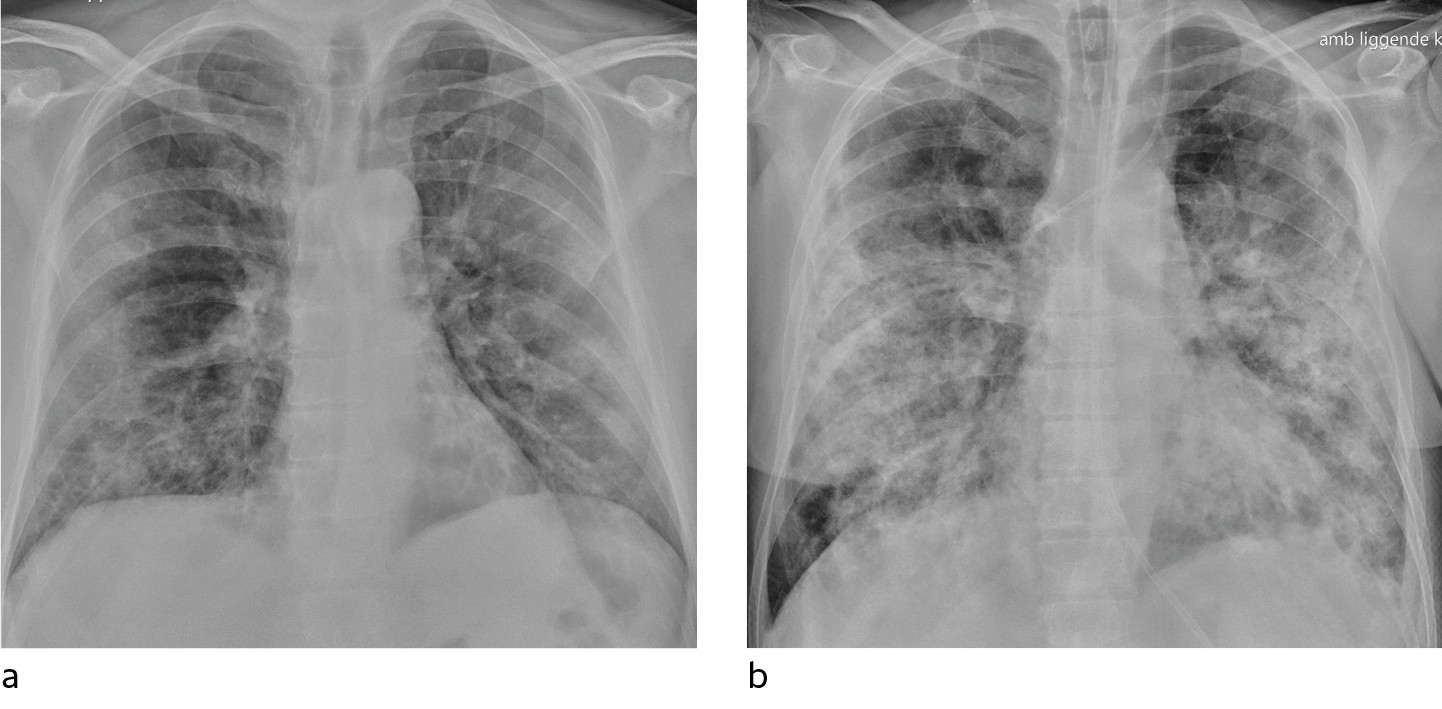

I et materiale fra Hongkong hadde 69 % funn på røntgen thorax før behandling (baseline), men 9 % hadde funn på røntgen thorax før positiv PCR (14). Sensitiviteten for røntgen thorax var 69 % og for PCR 91 %. Vanligste røntgenfunn var bilateral konsolidering og mattglassfortetninger med perifer og kaudal distribusjon. Forandringene var mest uttalt 10–12 dager etter symptomdebut. Figur 1 og figur 2 viser typiske funn på røntgen thorax ved covid-19.

Pasienter med moderate symptomer skal utredes med bildediagnostikk i tråd med rutiner for luftveissykdom. Røntgen thorax anbefales imidlertid ikke som primær modalitet for spesifikk diagnostikk av covid-19, fordi et normalt røntgenbilde ikke utelukker sykdommen og fordi typiske funn heller ikke er spesifikke nok til å bekrefte den. Røntgen thorax kan likevel være indisert med tanke på differensialdiagnostikk.

Hos inneliggende pasienter kan et sengebilde i tidlig stadium være nyttig som sammenligningsgrunnlag for tolking av bilder tatt senere. Hos pasienter med alvorlig sykdom vil det være indisert med sengebilder for kontroll av medisinskteknisk utstyr (figur 3), men det er ikke indisert med daglig, rutinemessig røntgen thorax hos stabile pasienter. I forløpet av sykdommen vil det være indisert med sengebilde ved mistanke om komplikasjoner og ved oppfølging og monitorering av sykdomsprogresjon.